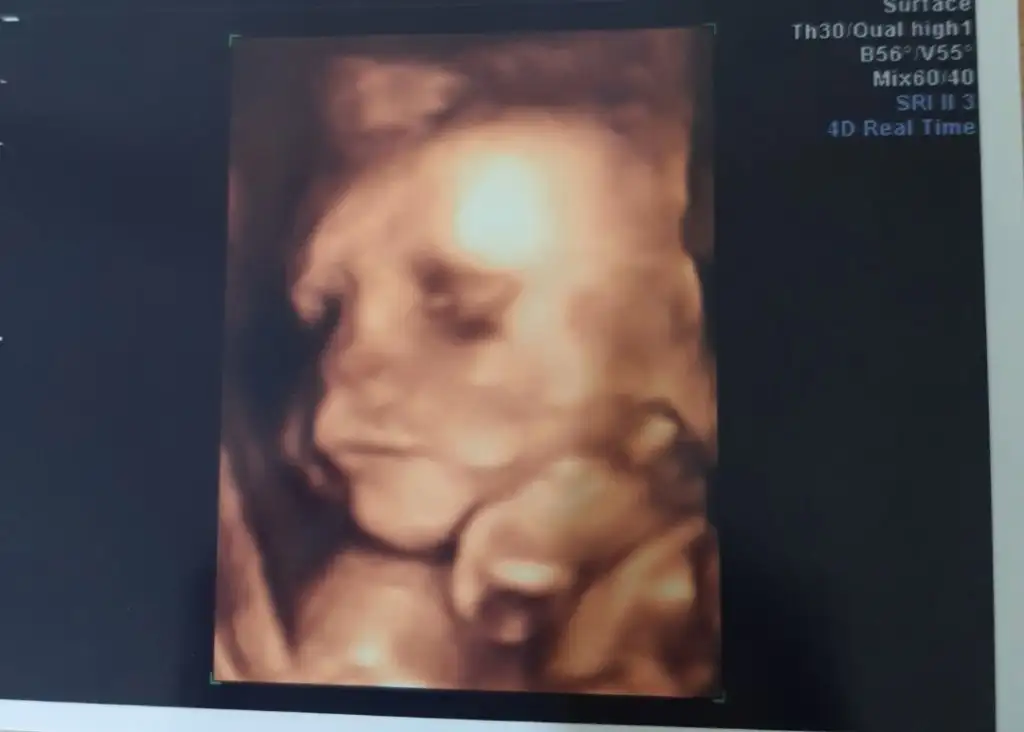

Slmlar herkese bizim bugun doktor ziyaret günümüzdu tam 26+0 810 grm 32 santimmisiz kafası sağ kaburgamın altindaymis ters duruyo dedi böbrek ağrın olursa panik yapma dedi bebis hep bi yerdeymis çünkü bu da resmimiz💕

• Screenshot_20220416-191852_Gallery.webp

Screenshot_20220416-191852_Gallery.webp

11 KB · Görüntüleme: 105